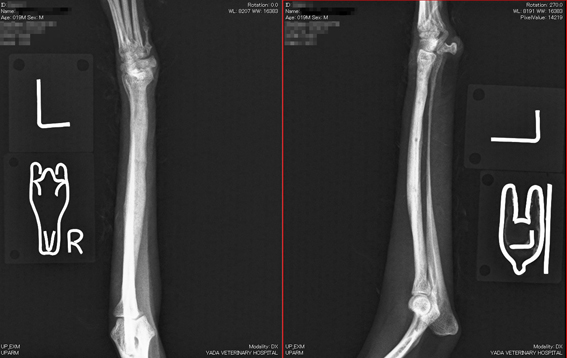

トイプードル

体重1.8kg、1歳4か月齢

左橈尺骨遠位の骨折。

写真1段目: 手術前

写真2段目: 手術後

写真3段目: ピン抜去直後

手術後1か月半で抜ピンしました。

写真4段目: ピン抜去1か月後